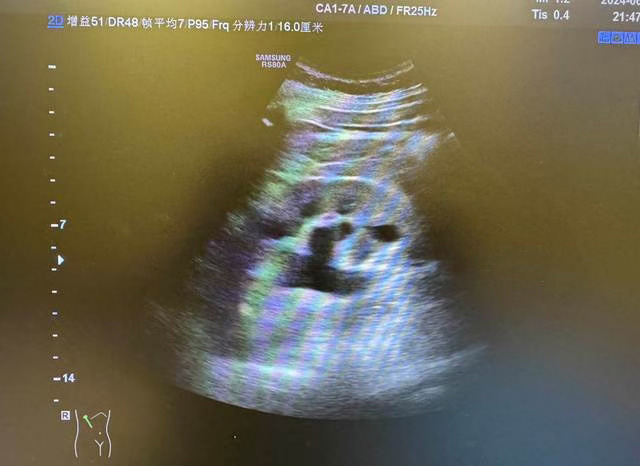

超聲檢查是其診斷的首選方法,因為超聲具有直觀、簡易、省時、無痛苦、無放射線等優(yōu)點,臨床上應(yīng)用廣泛。超聲能迅速判斷腎臟位置、外形、大小,在腎臟疾病的診斷、療效觀察和預(yù)后判斷方面有著十分重要的意義,現(xiàn)在已經(jīng)成為腎病患者的常規(guī)檢查。并且腎結(jié)石的體積都很小,有的呈泥沙狀,超聲在這方面分辨率非常高,在彩超下會顯示出非常明亮的強(qiáng)回聲團(tuán),并且在強(qiáng)回聲團(tuán)后方會有明顯的聲影。很小的腎結(jié)石在超聲下也可以檢查出,因此,腎結(jié)石在彩超下具有非常高的診斷率。但由于腸道內(nèi)容物對超聲具有干擾作用,超聲檢查輸尿管中下段結(jié)石的敏感性較低,可結(jié)合其他影像學(xué)檢查如CT檢查補(bǔ)充診斷。